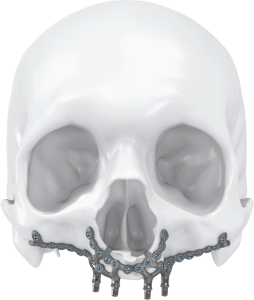

Los implantes subperiósticos o yuxtaóseos son dispositivos médicos utilizados en cirugía maxilofacial y dental para reemplazar dientes perdidos o para estabilizar prótesis dentales.

Estos implantes dentales se colocan debajo del tejido óseo que recubre la mandíbula o el maxilar superior, conocido como periostio, y proporcionan una base sólida y estable para la fijación de los dientes artificiales.

A diferencia de los implantes dentales convencionales que se insertan directamente en el hueso, los implantes subperiósticos se colocan debajo del periostio para aprovechar la mayor cantidad posible de superficie ósea disponible y proporcionar una mayor estabilidad.

Una vez preparado el lugar de colocación del implante dental, se colocará el implante subperióstico debajo del periostio y se asegurará con tornillos especiales.